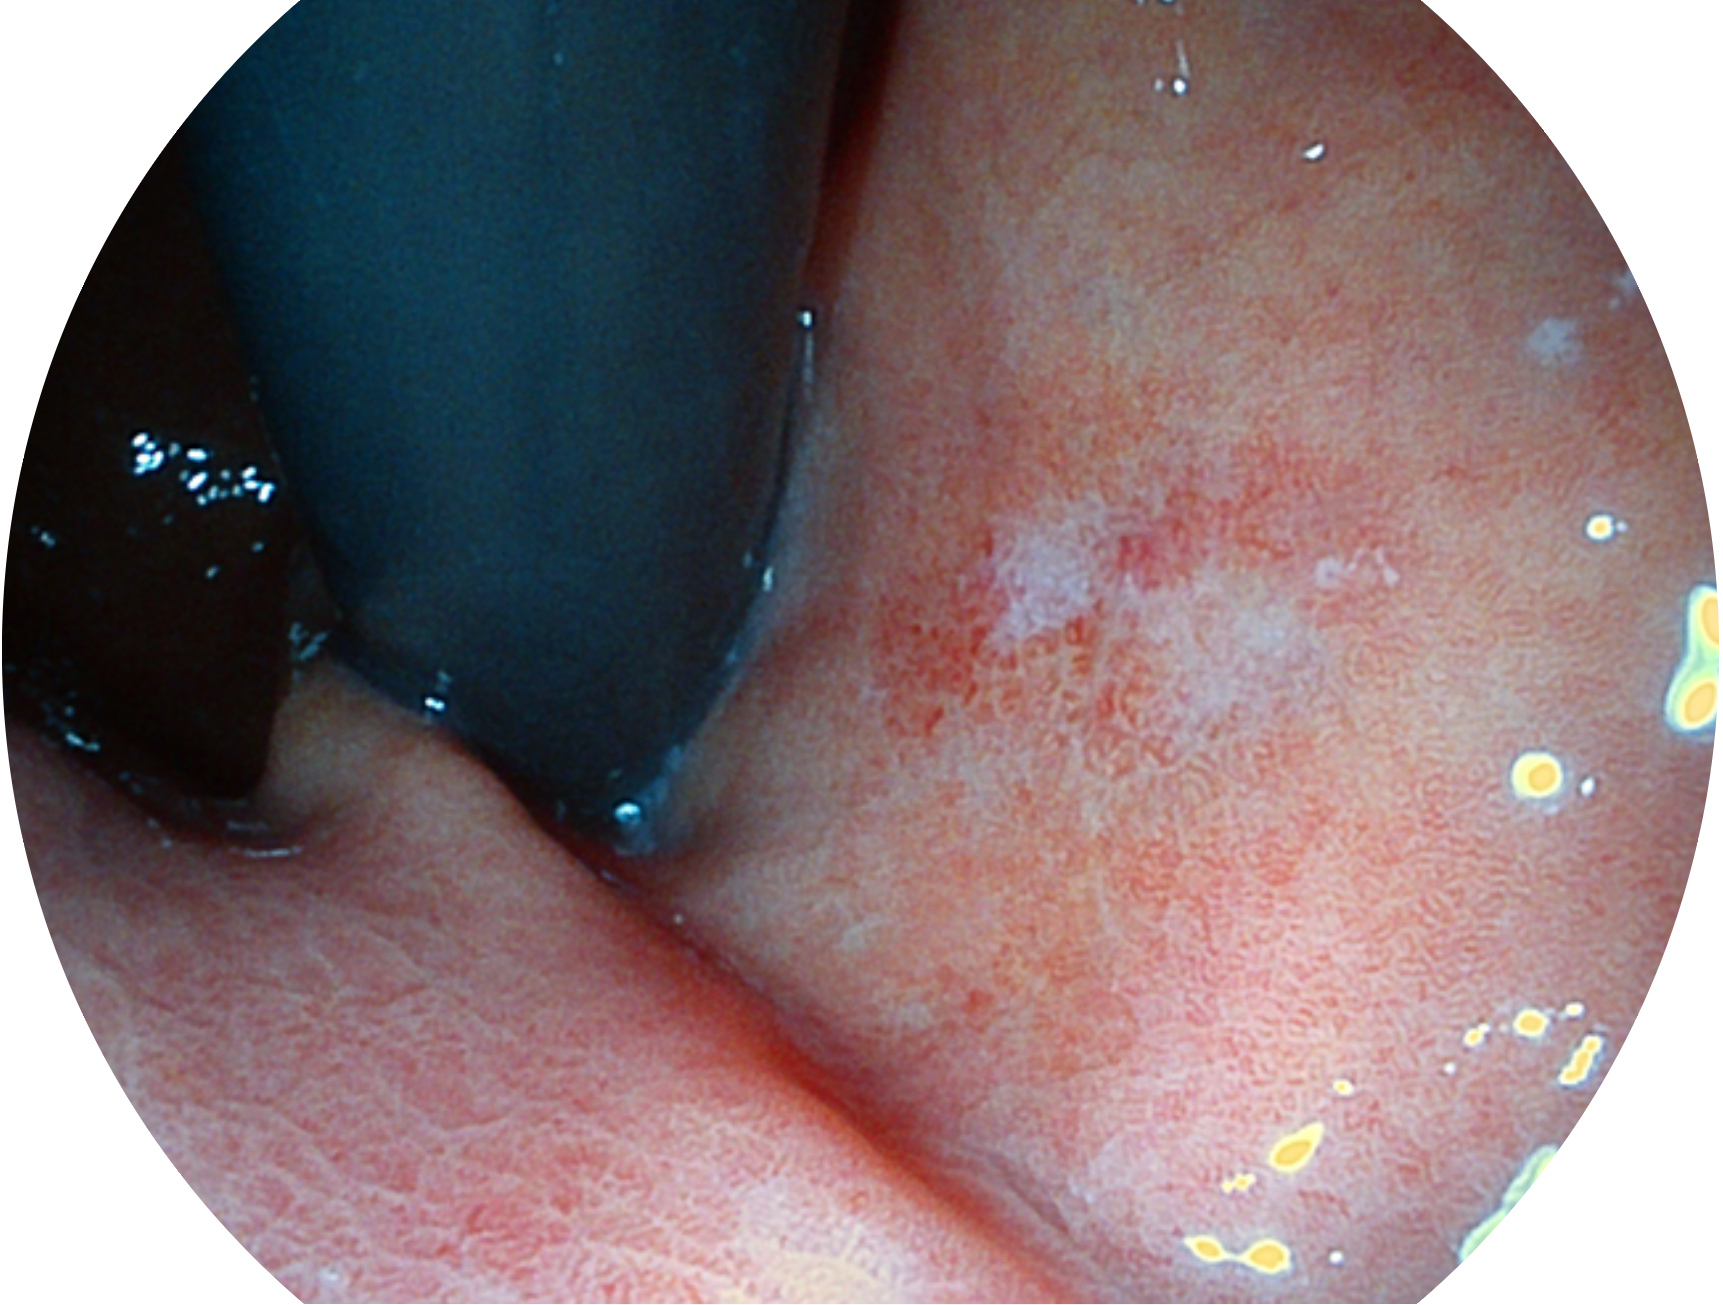

SFI技术是结合特定光谱照明与数字光谱滤波,实现高亮度特殊光成像。染色模式下,不改变粘液、食物残渣、粪液等基本颜色,在保持与白光照明相似的图像色调的同时突显了图像颜色的红白对比度,且在远距离观察的情况下具备与普通白光模式相同的图像亮度,有助于消化道疾病的大范围扫查和早癌筛查。

• 白光图像 SFI图像